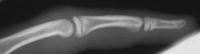

Case 1. 14 year old boy with radial prominence and ulnar deviation of the middle finger proximal interphalangeal joint. Painless, no history of trauma.

Radiographs showing well circumscribed calcification at the  proximal phalanx collateral ligament origin, 10 degrees of lateral angulation.